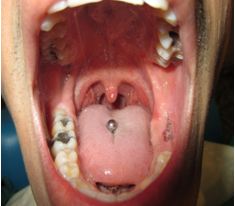

Se ha demostrado que los piercings colocados en la lengua (Figura2) provocan la recesión en la cara lingual de los incisivos antero-inferiores junto con un aumento en la profundidad de las bolsas periodontales; mientras que algunos de los piercings colocados en el labio inferior pueden provocar recesiones en la cara vestibular de los incisivos inferiores sin aumentar la profundidad de las bolsas periodontales5,7,9,15

Figura 2 Piercing colocado en la lengua que causó una Angina de Ludwig.